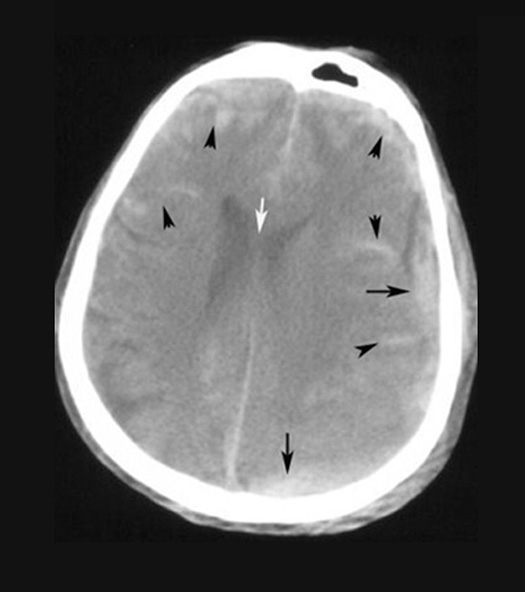

Subarachnoid Hemorrhage and Subdural Hemorrhage in a patient with head trauma.

Case 5:

Imaging findings:

Figure 5 : Pre-contrast axial CT

- Arrowheads point to subarachnoid blood in the sulci and SA space.

- Black arrow points to subdural blood.

- Normal sulci are filled with low density normal CSF and appear dark. Sulci filled with blood appear hyperdense.

- White arrow points to shift of midline to right.